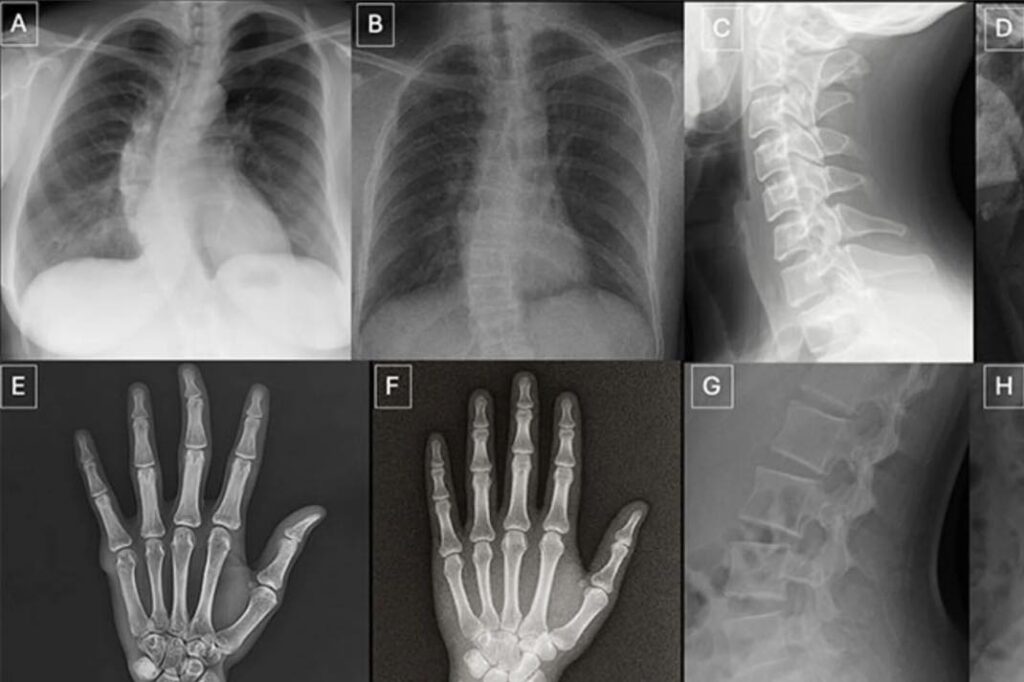

Ci-dessus : radiographies réelles et fausses générées par ChatGPT-4o, correspondant à la même anatomie. A, C, E et G sont réelles. Les autres sont des faux. © Radiological Society of North America (RSNA)

Le plus troublant est que ces faux ne se limitaient pas à des images grossières. Ces présentaient des structures anatomiques suffisamment cohérentes pour semer le doute, y compris chez des experts formés à l’analyse d’images complexes. Plus inquiétant encore, la même éttude montre également que certains modèles d’IA multimodaux – ici ChatGPT-4o/5, Google’s Gemini 2.5 Pro, et Meta’s Llama 4 Maverick – peinent à repérer les radiographies artificielles, y compris lorsqu’ils évaluent des images créées à l’aide de technologies proches, ce qui signifie qu’il n’existe pas à l’heure actuelle de systèmes capables de détecter de façon fiable les fausses radios générées par l’IA.

Face à cette montée des deepfakes médicaux, les chercheurs plaident pour la création d’outils de détection dédiés, de bases d’entraînement pédagogiques et de protocoles renforcés d’authentification des images. Certains indices reviennent déjà souvent dans les faux les plus convaincants : os trop lisses, colonne vertébrale anormalement droite, symétrie excessive des poumons ou fractures dessinées avec une netteté suspecte. Mais ces « marqueurs d’IA » ne suffiront pas longtemps à donner le change à mesure que les modèles génératifs progresseront (et ils progressent vite).